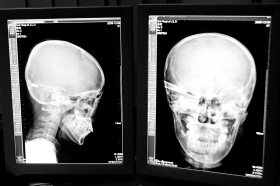

在接受x光檢查的小沖

“還是先做個(gè)X光透視,看一下箭桿到底有多深!毖劭漆t(yī)生緊急趕到CT室查看,和放射科的幾位醫(yī)生共同研究后,決定先讓小沖做X光透視。

“如果再用點(diǎn)力,就從后腦穿出來了!”由于小沖無法移動(dòng),醫(yī)生拿來移動(dòng)插座,將透視的光板放在小沖的移動(dòng)病床上,透視后讓在場的醫(yī)生都吃了一驚:箭桿直接穿過了大腦和小腦,箭尖兒直抵后顱骨,足足有10余厘米。

“從目前的情況看,必須請腦外科的專家來會診!笨催^小沖的片子,一位醫(yī)生皺緊了眉頭,神經(jīng)外科的專家問詢后也緊急趕到急診室。